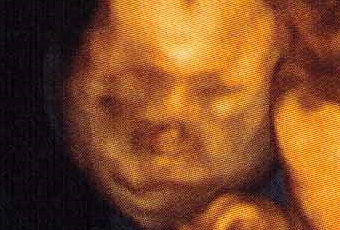

A estas alturas del embarazo, también me doy cuenta que en cuestión de 3 meses, seré responsable de otro pequeño ser a mi cargo, será otra experiencia completamente diferente, otra etapa a la que me enfrentaré.Solo espero que todo vaya bien, el resto irá surgiendo. Tengo ya ganas de ver su carita, me pregunto...sacará las orejas de soplillo de mi hermano?, será tan buena como mi pequeña? será tan guapo y listo como el padre? tan gracioso y simpático como la mami? romperá la tranquilidad que reina en casa con nosotros tres? jajajaja ayyyyy qué fácil es hacer niños....Solo espero poder entregarme con él como lo hice y hago con mi pequeña, para sentir que lo hago bien y que lo hago feliz...